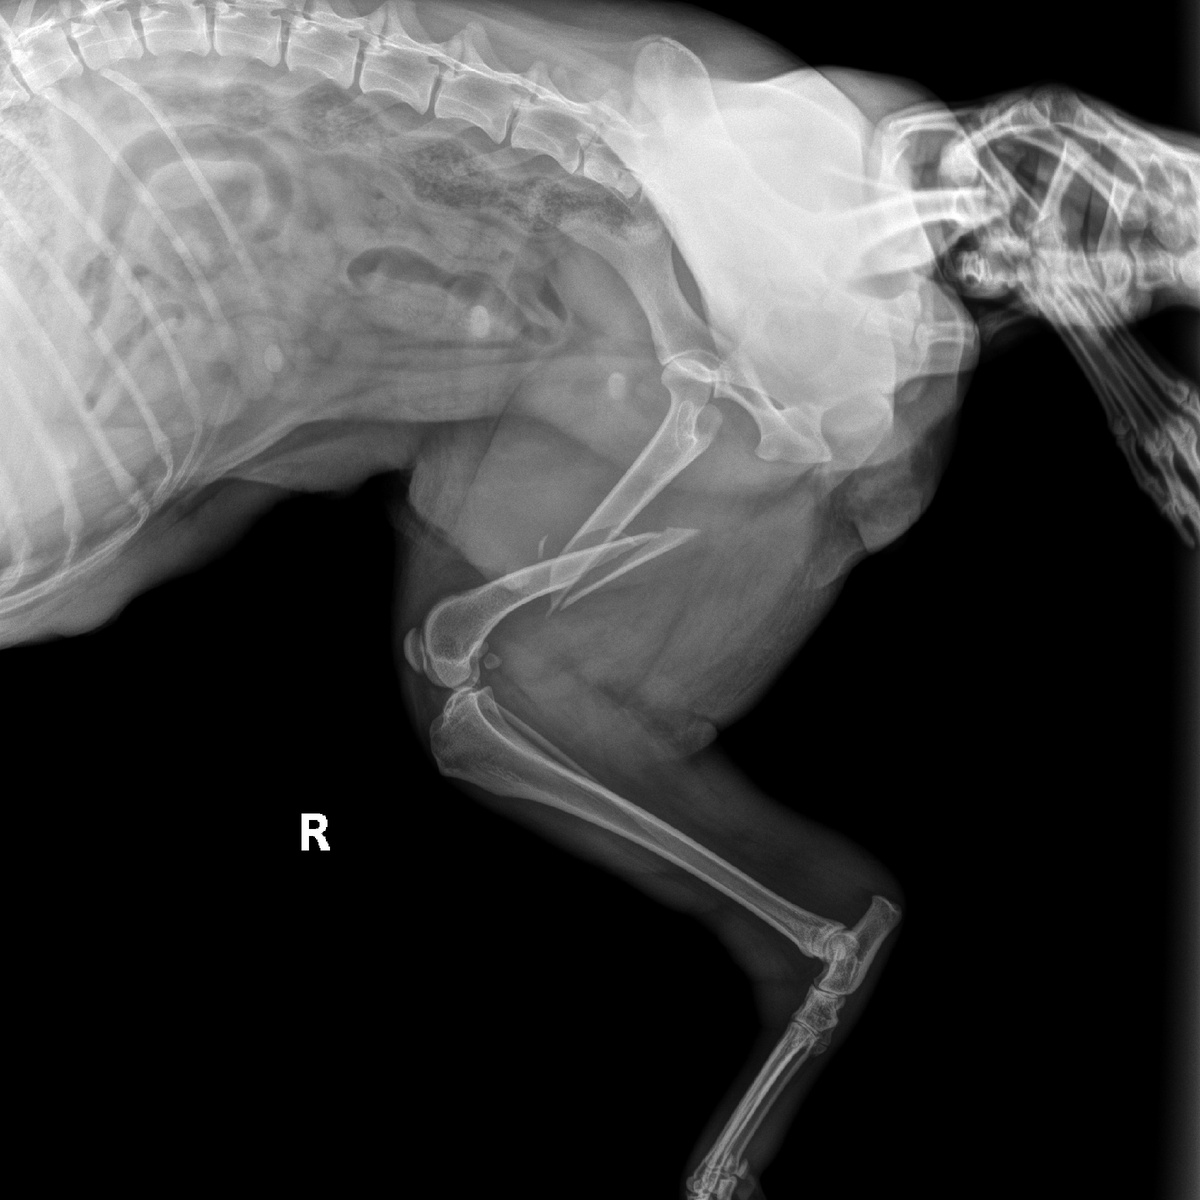

Мотютак (зовут эту собаку,) прооперировали, с диагнозом перелом тазовой кости, а у неё щенки которым по 1.5 мес. Очень жалко смотреть на то как ей больно, но малышей кормить нужно 😞, вот и прочность клетки, прутья разворотила, беды наделала... Кто может не проходите мимо поста, операция с долгом по Боцману 26.000 руб,оплатила 20.000 руб.Помощь приюту всегда актуальна. Финансово можно помочь переводом на наши реквизиты: ❗Карта ПСБ: 2200030502292973 ✅Привязана к номеру +7 (949) 417-86-70 БИК: 044525555 Корр. счет: 30101810400000000555 ИНН/КПП: 7744000912/997950001

Мотютак (зовут эту собаку,) прооперировали, с диагнозом перелом тазовой кости, а у неё щенки которым по 1.5 мес.

Очень жалко смотреть на то как ей больно, но малышей кормить нужно 😞, вот и прочность клетки, прутья разворотила, беды наделала...